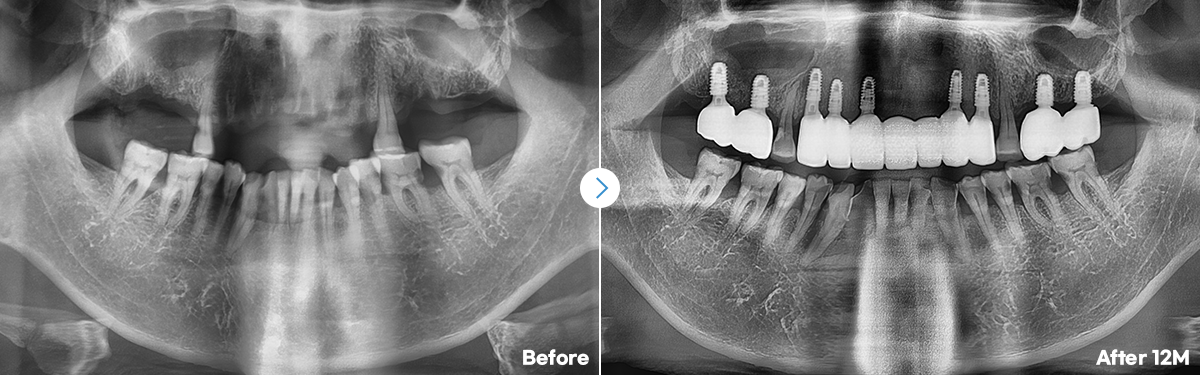

임플란트 개수가 많아도,

안정적이고 정확한 식립!

오차없이 초정밀 식립 3D 데이터로 철저한 수술계획네비게이션 임플란트